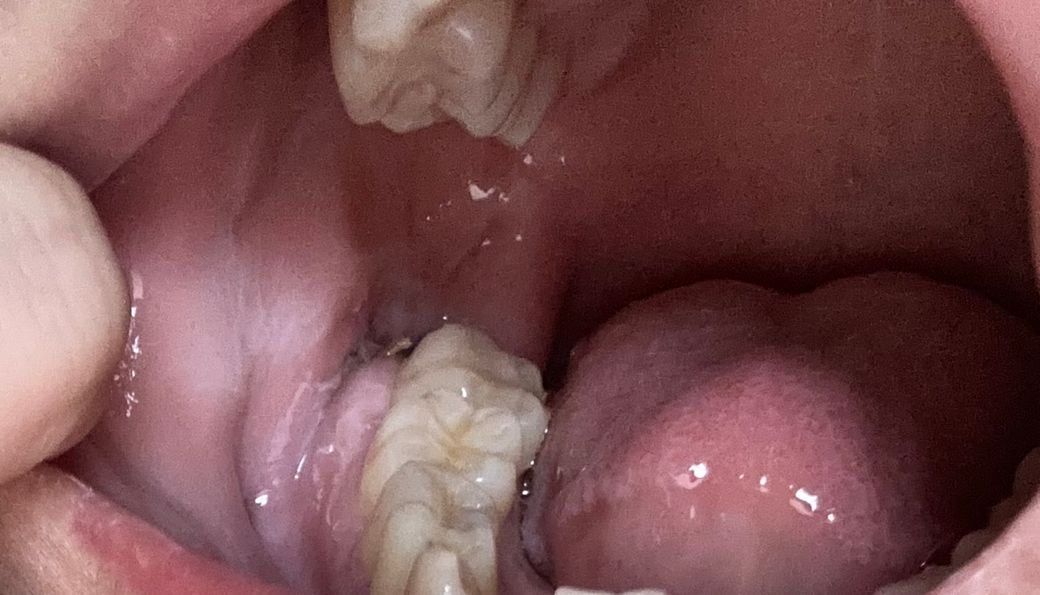

수요일에 왼쪽 아래 매복사랑니 발치하고 3일째입니다 녹는실을 쓰셨다고 치과는 다시 내원 안한다고 하셨는데 지금 염증 하나 없이 잘 낫고 있는게 맞는건가요 ?̊̈ ?̊̈

그리고 뭔가 걸리적거리는데 이게 같은건 뭘까요 여긴 가글 처방을 안해주셔서 최대한 안닿게 닦고는 있지만 ㅠㅠ 어제 삼겹살을 먹었는데 저게 삼겹살 낀건지 아님 실인지를 모르겠네요 갑자기 걸리적거리는데,,

이게 삼겹살 먹기 전인데 그냥 실인걸까요?

• 2번 째 사진

이정도면 정상적으로 아물고 있는 것입니다. 혹시 음식물 잔사가 낄 수도 있지만 그냥 두면 저절로 빠집니다.

사진상으로 보면 잘 아물고 잇는거 같으니 크게 걱정은 안하셔도 될것같습니다. 최대한 음식물만 남지 않도록 관리를 해주세요.

1. 염증의 양상은 특별히 보이지 않습니다

2. 양치질 살살 해주셔도 됩니다 음식물이 안끼어 있어야 치유가 빨리됩니다